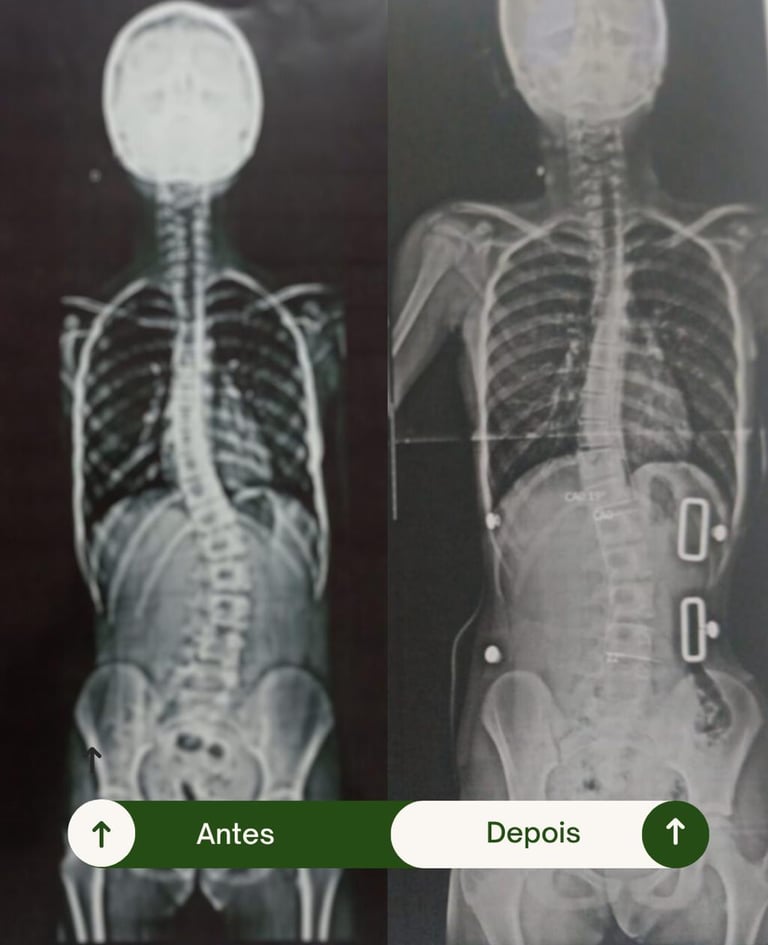

Resultados Comprovados

Transformando vidas por meio da fisioterapia e da tecnologia 3D.

Veja como nossos pacientes reconquistaram mobilidade, conforto e confiança.